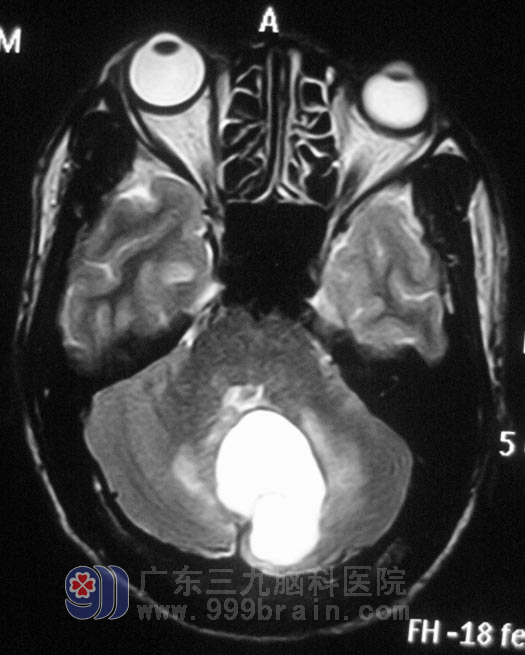

在广东三九脑科医院头颅MR检查提示:1.左侧小脑半球囊性占位性病变;2.小脑扁桃体下疝畸形。行进一步的MR增强检查,囊性强化,鲁明主任考虑囊性星形细胞瘤,不排除血管网织细胞瘤的可能。